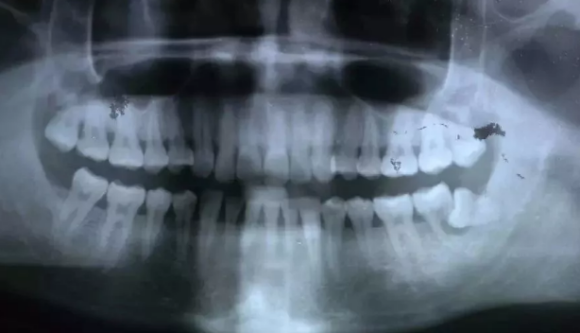

阻生牙把前面的牙齿顶坏了,两个牙齿都需要拔除

被阻生牙顶坏的相邻牙无法治疗,只能拔除了,非常可惜!